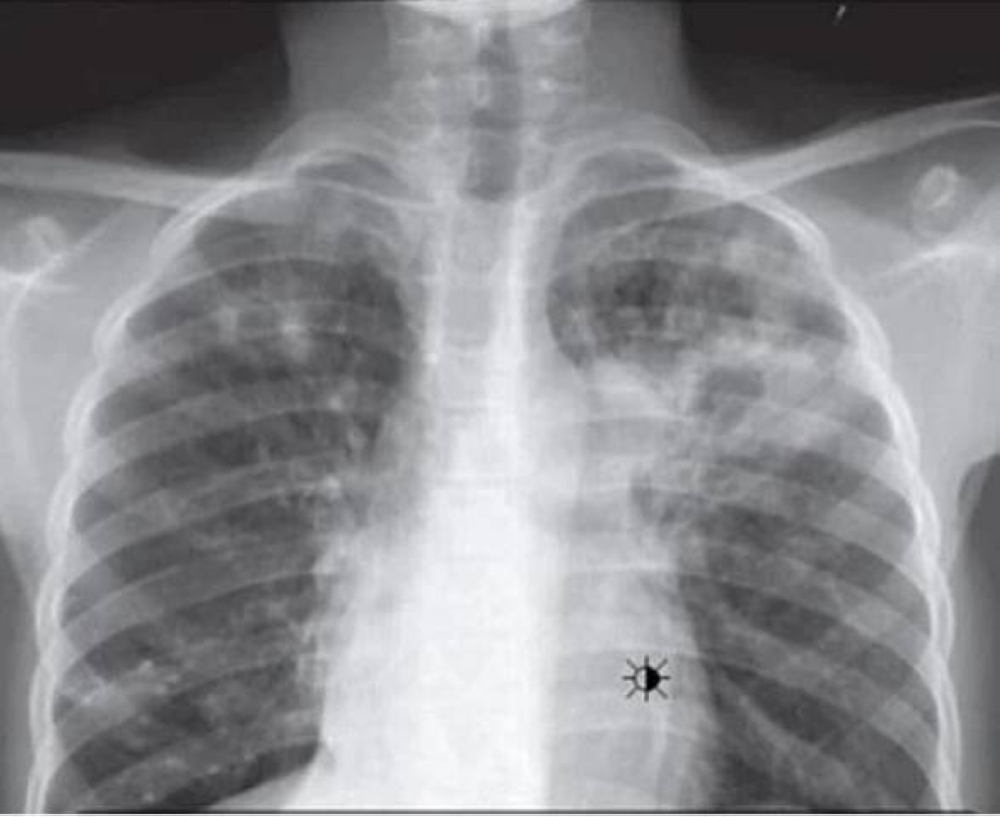

أسهمت الجهود الصحية في المملكة، في انخفاض حالات الإصابة بالدرن الرئوي، حيث سجلت انخفاضًا للعام الثاني على التوالي، وانخفضت حالات الدرن الرئوي في العام الماضي بـ3%، حيث بلغت 1964 حالة درن رئوي، مقابل 2017 حالة في 2023، في وقت تصدرت منطقة الرياض أكثر حالات الدرن الرئوي كأكثر مناطق المملكة حالات بـ24%، وفاقت حالات الذكور السعوديين، حالات الدرن الرئوي للإناث السعوديات بـ76% للذكور مقابل 24% للإناث السعوديات.

كشف تقرير وزارة الصحة لعام 2024، حالات الدرن الرئوي بفروع ومكاتب وزارة الصحة، حيث سجلت 1964 حالة درن رئوي، منها 1065 حالة السعوديين بـ54%، مقابل 899 حالة الأجانب، وسجلت حالات الذكور السعوديين 806 حالات بـ76%، مقابل 259 حالة السعوديات بـ24%، بينما سجلت حالات الذكور الأجانب 624 حالة بـ69%، مقابل 275 حالة الأجنبيات بـ31%.

وتصدرت الفئة العمرية من 25-35 سنة أكثر الفئات العمرية حالات الدرن الرئوي بـ567 إصابة، وحلت الفئة العمرية من 35-45 سنة ثانيًا بـ396 إصابة، والفئة العمرية من 15-25 سنة ثالثًا بـ303 إصابات، والفئة العمرية من 45-55 سنة رابعًا بـ257 إصابة، وتساوت الفئتان العمريتان من 55-65 سنة، وأكثر من 65 سنة خامسًا بـ192 إصابة.